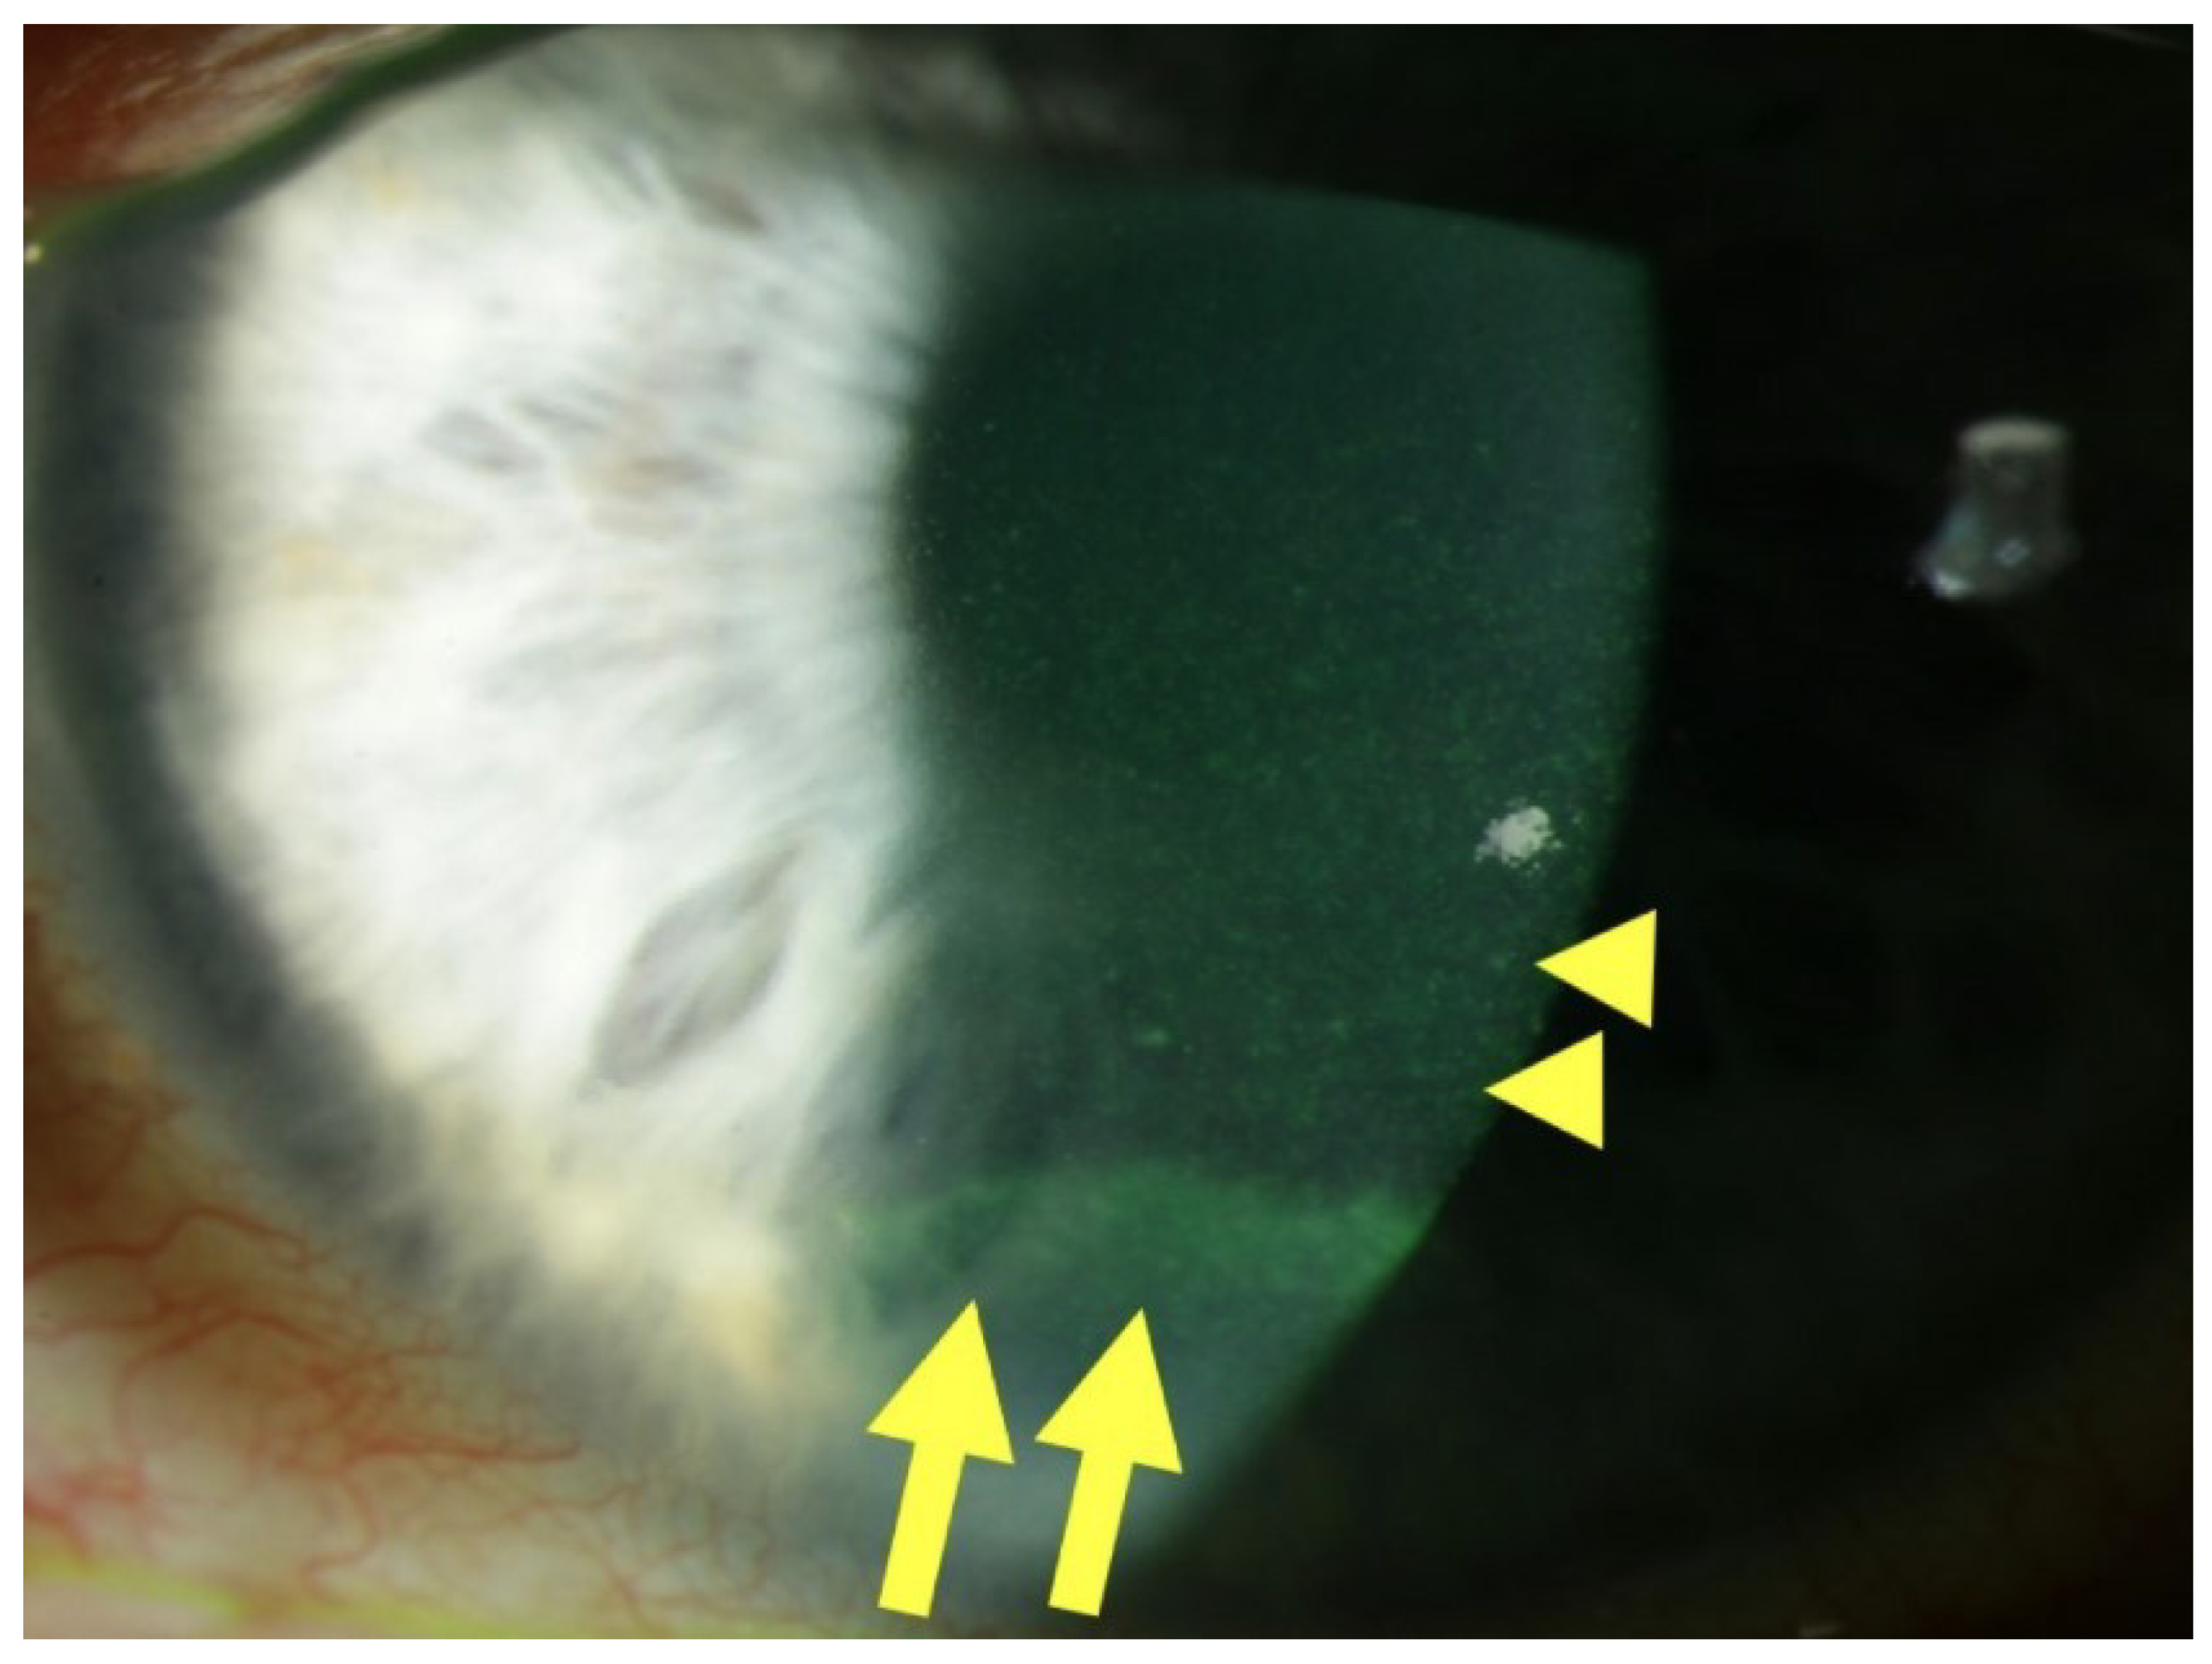

DEK manifests through a spectrum of clinical signs arising from epithelial dysfunction. A hallmark finding is superficial punctate keratitis (SPK), characterized by fluorescein-positive punctate epithelial erosions. A slit-lamp photograph suggestive of surface changes associated with DEK is shown in Figure 1.

These lesions represent the breakdown of the corneal epithelial surface, often presenting as fine, scattered yellow or white dots on slit-lamp examination. Epithelial fragility and recurrent erosions are another characteristic feature. Diabetic neuropathy can lead to decreased corneal sensitivity, making the eye vulnerable to minor injuries that may go unnoticed. This, coupled with impaired epithelial healing, contributes to recurrent epithelial defects that can be painful and disruptive to vision. These clinical signs highlight the compromised epithelial integrity associated with diabetic keratopathy.

Figure 1. Slit lamp photograph of a patient with diabetic keratopathy. Centrally, fluorescein staining reveals SPKs (yellow arrowheads), as well as an epithelial ridge or pseudo-dendrite, indicative of a recently closed erosion (yellow arrows), in the inferior third of the cornea. From “Diabetic Keratopathy: Redox Signaling Pathways and Therapeutic Prospects” by Buonfiglio, F.; Wasielica-Poslednik, J.; Pfeiffer, N.; Gericke, A. Antioxidants 2024, 13, 120, Introduction, Figure 1, (https://doi.org/10.3390/antiox13010120 (accessed on the 11 March 2024)). CC BY. [4].